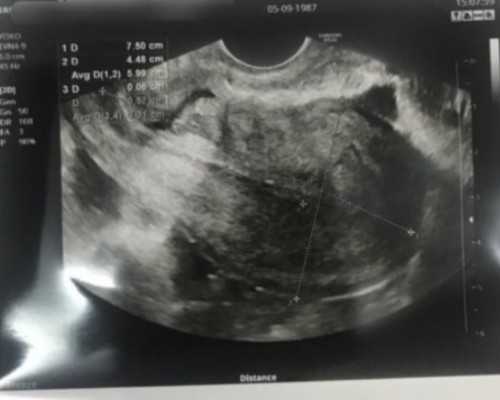

在胚胎移植后,试管准妈妈再等待7-14天左右就可以够抽血验孕啦,通过检测血液中的HCG含量,就可以判断胚胎是否已经成功着床。

HCG在受精后第6天后由滋养细胞微量分泌,在受精后第10日后就可从母体血清中测出,是目前诊断早孕最敏感的方法。所以通过HCG了解胚胎发育情况,是判断是否成功妊娠的重要指标之一。